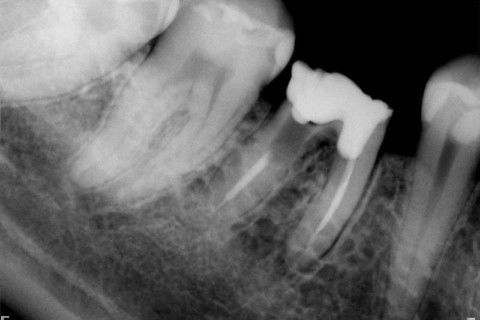

Retratamento de Canal, Tratamento de Perfuração, Restauração Provisória com Resina, Núcleo e Provisório.

RETRATAMENTO DE CANAL, TRATAMENTO DE PERFURAÇÃO, RESTAURAÇÃO PROVISÓRIA COM RESINA, NUCLEO E PROVISÓRIO.